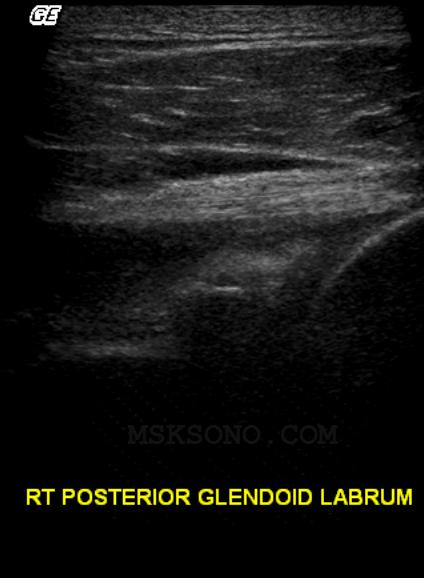

Posterior Glenoid

Labrum neutral

view, arm resting

over abdomen

with the elbow

bent at 90 deg.

Arm bent at 90, externally

rotated slowly shows

anechoic fluid benieth the

Infraspinatus tendon, with

echogenic material anterior

to the posterior glenoid

labrum capsule.  Could be

indicative of blood in joint

capsule.